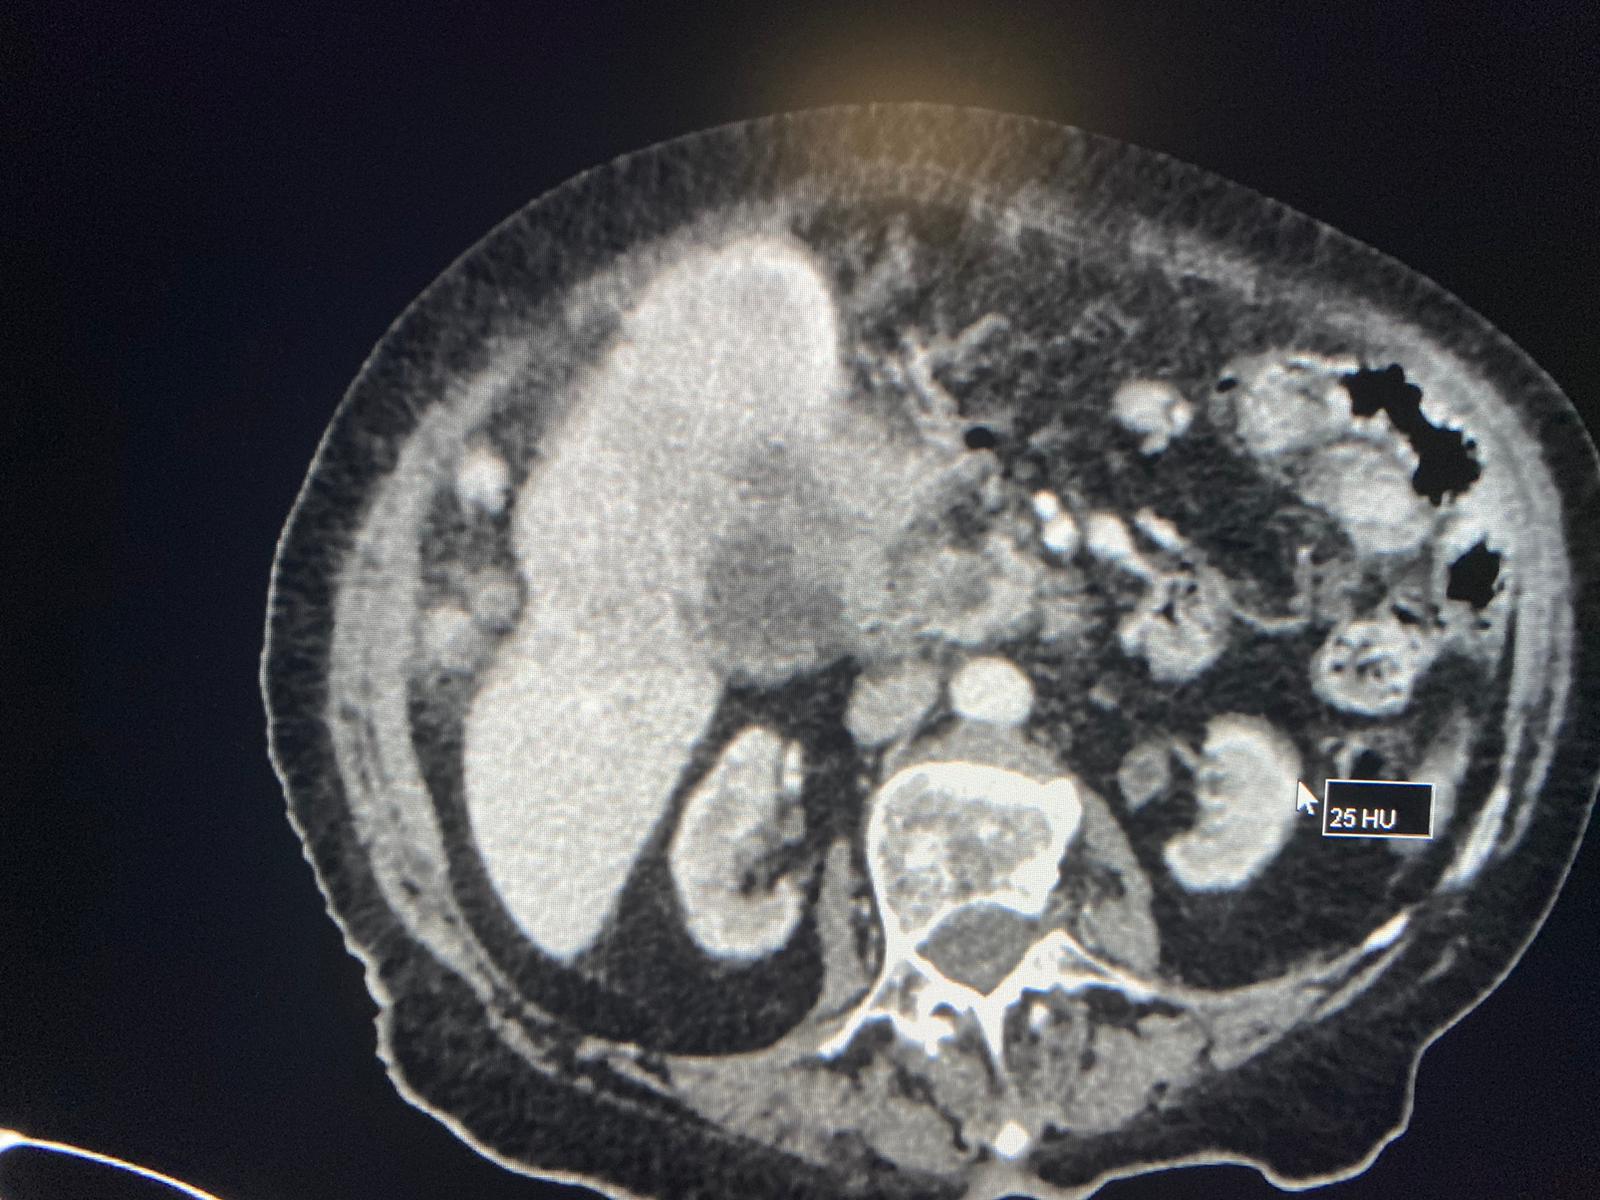

| Llaman por sospecha de colecisitis en mujer de 95 años. Se hace el TC y vemos una gran masa heterogènea hepática, que condiciona dilatación de via biliar intra y extra, junto con múltiples implantes perihepàticos, periportales, periesofágicos, intrapelvicos… Se sospecha de colangiocarcinoma, menos probable hepatocarcinoma. |